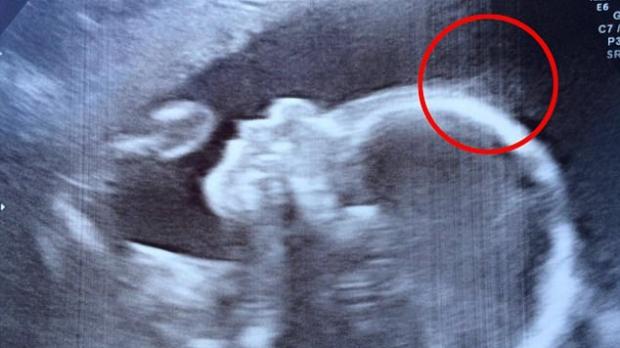

15 a 15 a saptamana de sarcina greturile matinale si starile de oboseala au disparut aproape complet. Se dezvolta scheletul care va deveni vizibil la ecografie. Esti in plin carusel hormonal treci de la o stare la alta. Sistemul lui osos este din ce in ce mai puternic iar corpul micutului este acoperit de un strat de puf ce dispare pana in luna a opta numit lanugo.

Acest proces il va ajuta la dezvoltarea alveolelor din plamanii sai si a sistemului digestiv. Fetusul in saptamana a 15 a. Sarcina la 15 saptamani. In saptamana 15 de sarcina sau la 13 saptamani de la conceptie copilul creste rapid.

Sarcina 15 saptamani ecograf. Mamica totul despre sarcina sarcina in 40 de saptamani saptamana 15 de sarcina. Saptamana 15 de sarcina. In saptamana 15 de sarcina ritmul de crestere al bebelusului este unul alert asa cum o demonstreaza si vasele de sange tot mai intens ramificate ce sunt desenate pe pielea lui inca transparenta. Dar este important sa ai o alimentatie bogata in calciu pentru ca bebelusul iti ia din rezerve.